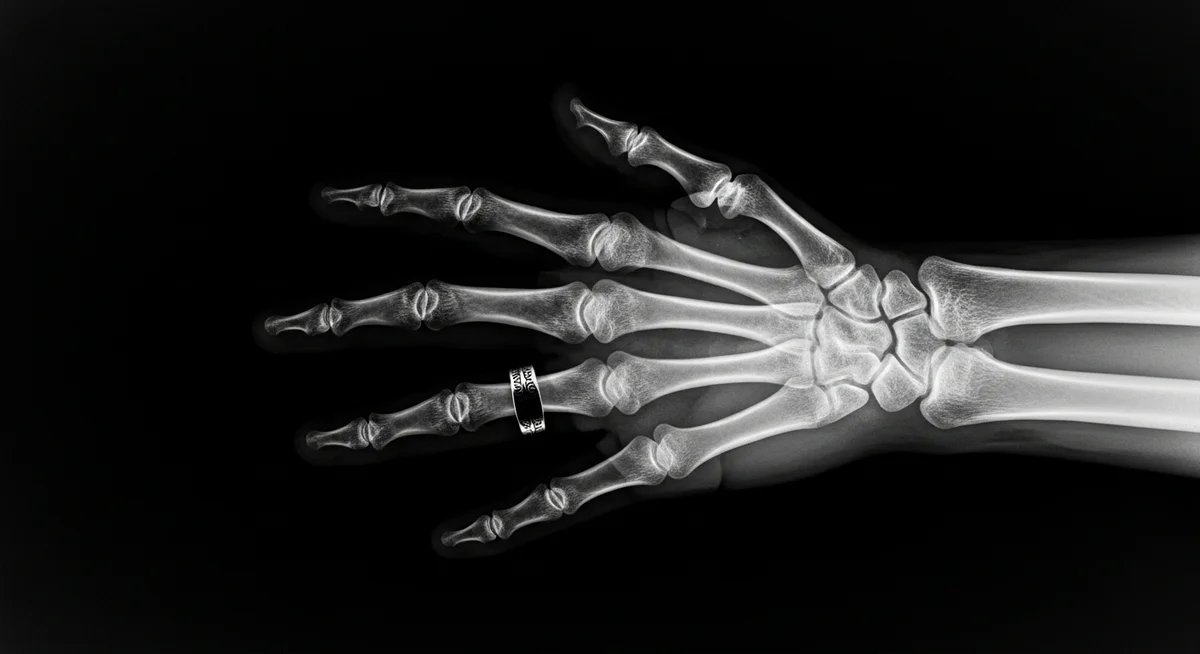

Röntgen, bu yeni ışınlara “X-ışınları” adını verdi, çünkü doğası hakkında henüz bir bilgiye sahip değildi. Keşfini duyurduktan kısa süre sonra, X-ışınlarının tıbbi görüntüleme alanında kullanılabileceği anlaşıldı. Röntgen, kendi eşinin elinin X-ışını görüntüsünü çekerek, bu alandaki potansiyeli gözler önüne serdi.

Wilhelm Röntgen’in X-ışınlarını keşfi, tıp alanında devrim niteliğinde değişikliklere yol açtı. X-ışınları sayesinde, doktorlar insan vücudunun içini ameliyatsız bir şekilde görüntüleyebilme imkanı buldu. Bu, kırıkların teşhisi, tümörlerin tespiti ve iç organların incelenmesi gibi birçok alanda önemli gelişmelere yol açtı.

Günümüzde X-ışınları, tıp alanında hala yaygın olarak kullanılmaktadır. Röntgen filmleri, bilgisayarlı tomografi (BT) taramaları ve mamografiler gibi yöntemler, X-ışınları teknolojisine dayanmaktadır. Ayrıca, diş hekimliğinde de dişlerin ve çene kemiğinin görüntülenmesinde X-ışınlarından yararlanılmaktadır.